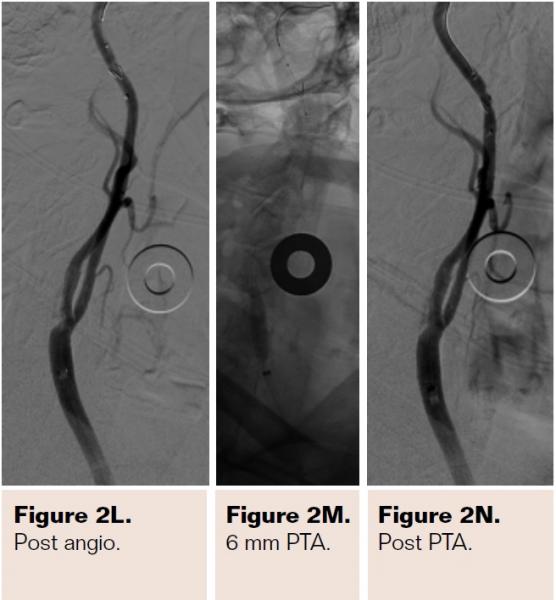

Pretreatment with dual-antiplatelet therapy (DAPT) was started 4 days prior to the procedure with aspirin and clopidogrel, with 600 mg loading dose of clopidogrel and 80 mg dose of atorvastatin the morning of the procedure. The right radial artery was accessed with a 6 Fr Terumo radial sheath, but intraarterial nitroglycerin was not administered due to a prior history of profound hypotension with sublingual nitroglycerin. Verapamil was withheld due to a systolic blood pressure of 130 mm Hg. Both right and left anterior oblique arch aortograms with a 5 Fr straight pigtail catheter demonstrated patency of the proximal great vessels, a type I aortic arch, and a calcified proximal right internal carotid artery (ICA) high-grade stenosis with patent right external carotid artery (ECA). The right common carotid artery (CCA) was selected with 5 Fr internal mammary (IM) diagnostic catheter that confirmed an 85% proximal right ICA stenosis. A soft-angled .035˝ Glidewire (Terumo) was advanced into the right ECA, exchanged out for an Amplatz .035˝ super-stiff wire (Boston Scientific), followed by removal of the diagnostic catheter, and radial sheath. A 6 Fr Shuttle sheath (Cook Medical) was delivered into the distal right CCA. After intracranial angiography, a NAV-6 Emboshield (Abbott Vascular) was deployed in the distal extracranial ICA, followed by predilation with a 4 x 30 mm Trek (Abbott Vascular), and deployment of a 7 x 30 mm Precise self-expanding stent (Cordis). Postdilation was performed with a 5 x 20 mm Maverick NC balloon (Boston Scientific), and then with a 6 x 20 mm Aviator balloon (Cordis) in order to then deliver the retrieval catheter. After repeat angiography confirmed an excellent result, the Shuttle was removed, and hemostasis achieved with TR band (Terumo) (Figures 2A-2R).